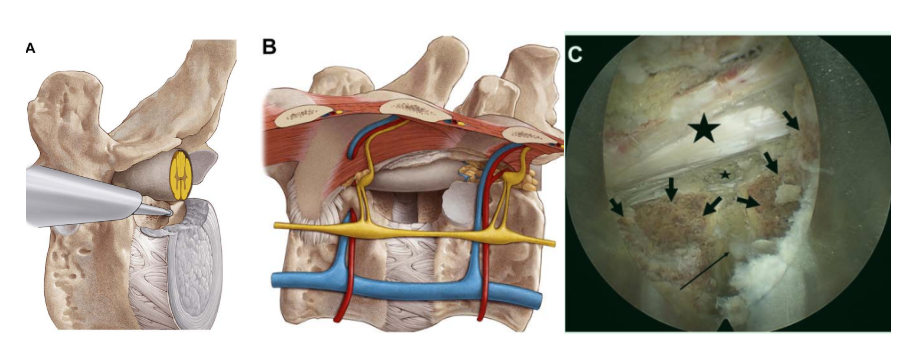

A, B.肋骨头(箭头)术中视图,打开椎间盘(电极内)(A),开始切除肋骨头(B)

A, B.椎弓根切除开始(A)和术中视图,包括切除椎弓根(小星号)、仍保留的椎弓根内侧皮质骨(短箭头)、切除的肋骨头(大星号)和硬膜外脂肪(长箭头)(B)

A, B切除椎弓根内侧皮质骨后术中视图,切除椎弓根(小星号),进入椎管(大星号),下位椎体(小箭头),椎间隙(长箭头)(A, B)

术中C臂透视,可见到达脊髓前方对侧

A-C 切除近端椎体和椎间盘尾侧的后缘骨质,直到脊髓前方从同侧到对侧实现足够的减压(A, B),即“盒状切除”。术中见脊髓前方(大星号)、椎间隙(长箭头)、盒状切除的上下椎体后缘(小箭头)、椎管对侧边缘(小星号)(C)。